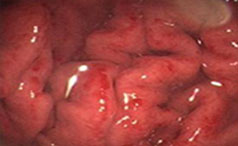

胃 病

常见症状:恶心呕吐、食欲减退

餐后饱胀、反酸嗳气